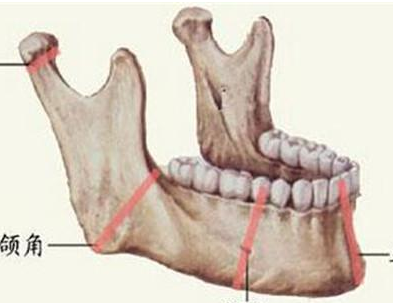

Sau phẫu thuật, hàm dưới bên trái của bệnh nhân trở nên yếu hơn. Vì vậy được chỉ định là cần phải bảo vệ hàm một cách tối đa, tránh những va đập mạnh có thể sẽ gây gãy xương.

Trường hợp nặng có thể là áp xe não, nhiễm khuẩn máu và các biến chứng nghiêm trọng khác, như trong trường hợp nam thanh niên này bị đau răng gây ra hoại tử hàm dưới với một diện tích lớn, mặc dù đã cố gắng điều trị, nhưng hàm dưới vẫn bị tổn hại nghiêm trọng. Cả đời sau đó phải chú ý tránh các cú va chạm bên ngoài gây ra tai nạn và các tình huống bất ngờ khác (có thể gãy hàm).